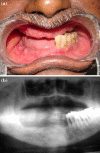

The conventional modality of treatment of partial edentulousness with reduced number of teeth was to render them complete edentulous and provide them complete denture or an overdenture with support of few remaining teeth. The goal of maintenance of roots are to prevent alveolar bone resorption, provide better load transmission, maintain sensory feedback and achieve better stability of denture with emphasis on psychological aspect of not being completely edentulous. Over the recent past titanium dental implants have been successfully used as tooth replacement with predictable results. A combination of tooth and implant support is well documented for fixed partial dentures but rarely for overdentures. This clinical report aims at evaluation of tooth root and implant supported mandibular overdenture treatment with telescopic coping.